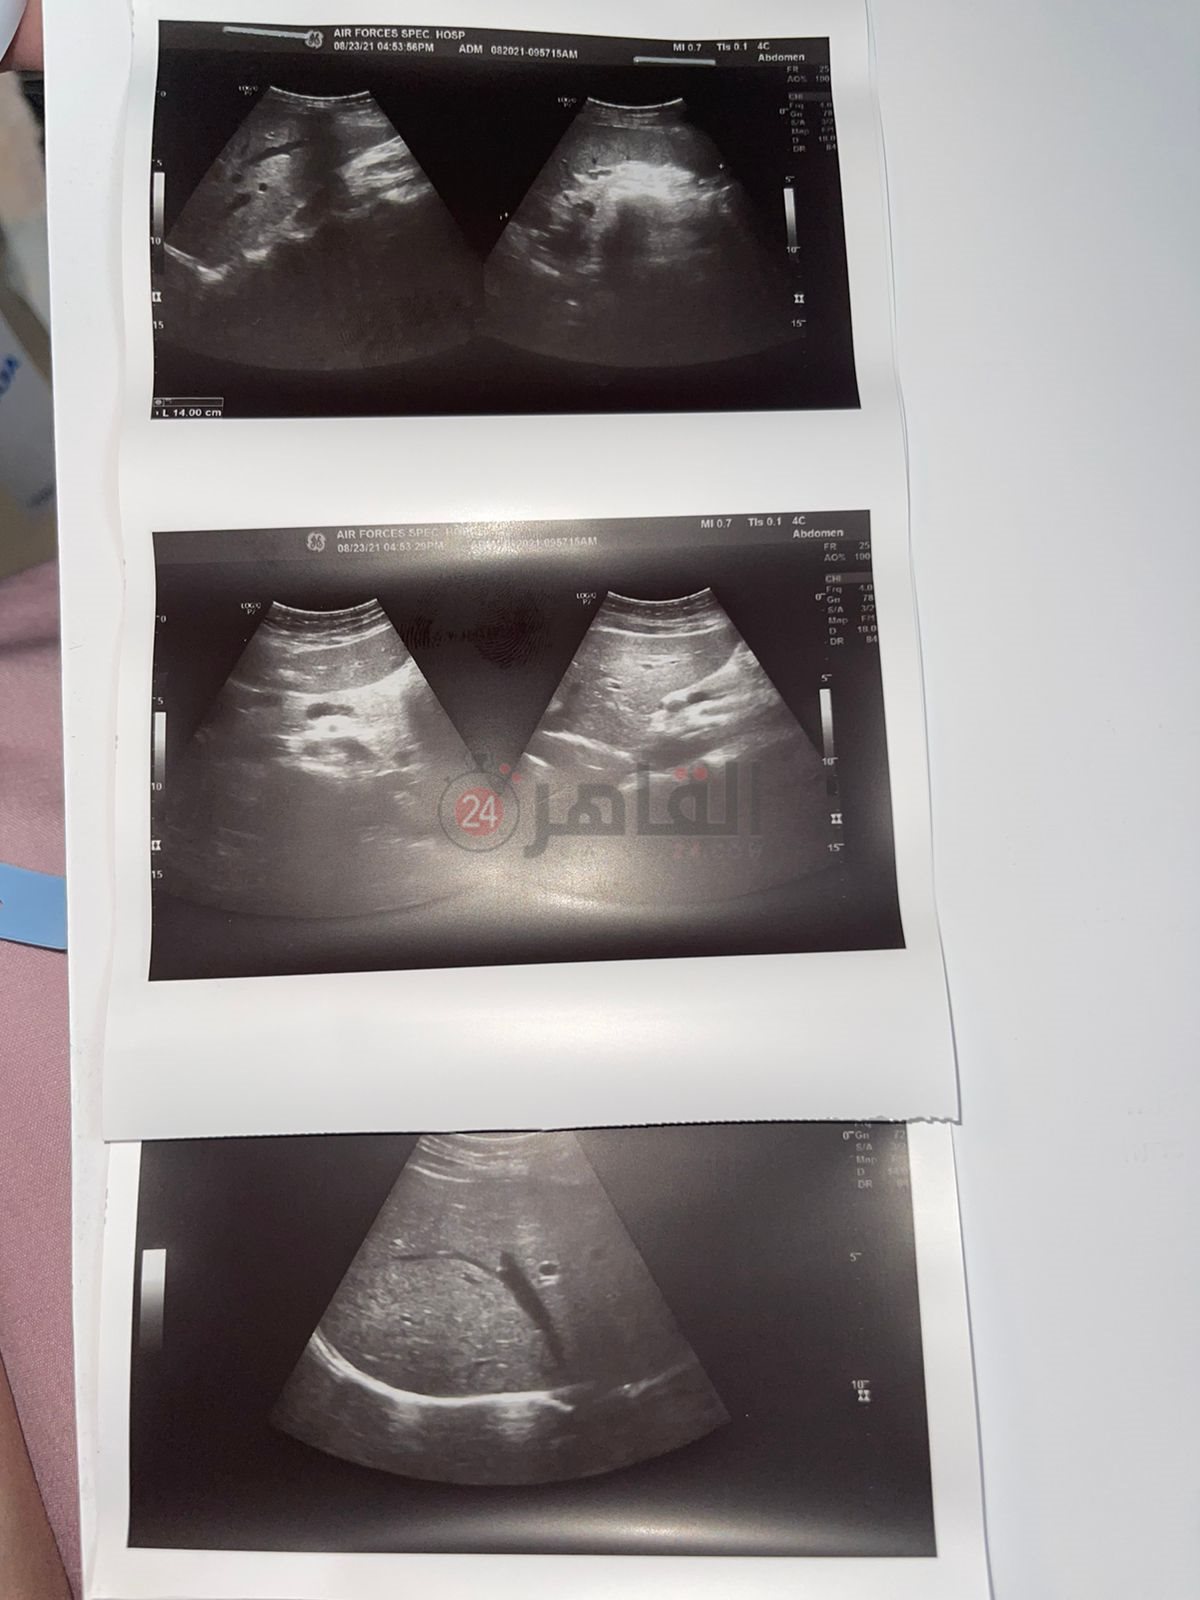

وأضافت في تصريحات خاصة لـ«القاهرة 24»، أن والدتها سهر يعودي التي تبلغ من العمر 73 عامًا، تعرضت للالتهاب الرئوي الشديد، مع ظهور بقع في الرئة اليمنى، مما أدى إلى احتجازها في المستشفى، كما وصلت نسبة الأكسجين في الدم إلى 77%.